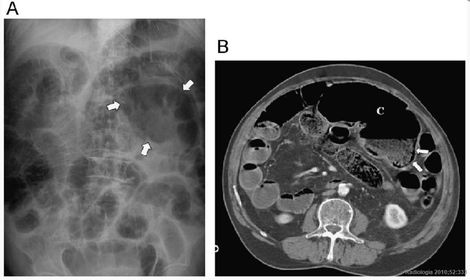

ISQUEMIA MESENTÉRICA

OBSTRUCCIÓN DEL INTESTINO DELGADO